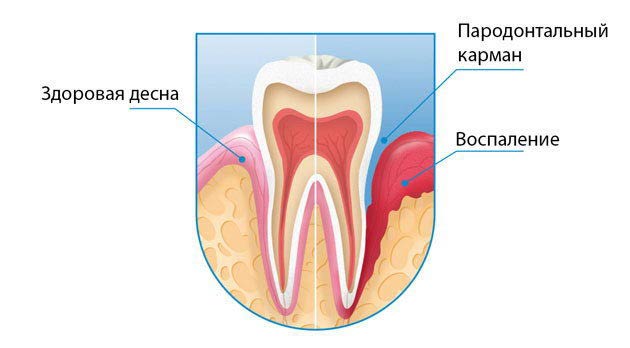

Запальний процес, що виник в тканини ясен з різних причин, сприяє її атрофії і відшарування від поверхні зубного кореня. В результаті утворюється вільний простір між яснами і тілом зуба – пародонтальні кишені.

З плином часу він заповнюється харчовими частинками, гнійними виділеннями, зубним нальотом і всім, що виявляється в роті.

Тривале знаходження цих мас в області зубного кишені викликає подальше поширення запалення і здатне привести до втрати зуба.